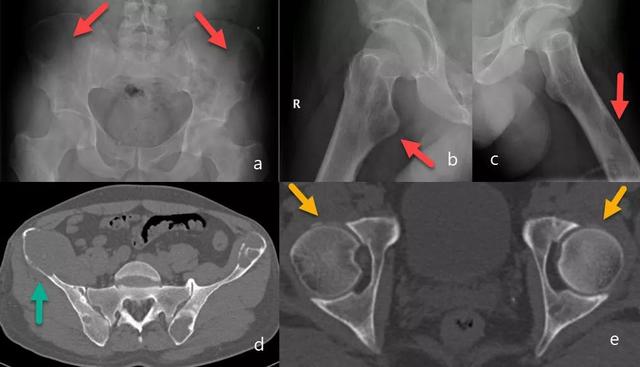

图7:骨盆X线片(a):跛行和右侧髋部疼痛的患者,右侧股骨近端明确的溶骨性病变(黄色箭头),皮质破坏。在CT研究(b,c,d和e)中,观察到多个明确边界的皮质下溶骨性病变(红色箭头),提示多发性骨髓瘤。通过骨活检确认诊断。

图13:棕色瘤。正位骨盆和轴向两侧髋关节X线片:髂嵴和股骨上的骨溶解性病变(红色箭头)(a,b和c)。在CT上,右髂嵴病变有皮质溶解和相关的软组织肿块(绿色箭头),以及其他明确边缘的病变,一些可见硬化边缘(d)。我们发现右侧髋部的软骨钙质沉着症(黄色箭头)(e)。